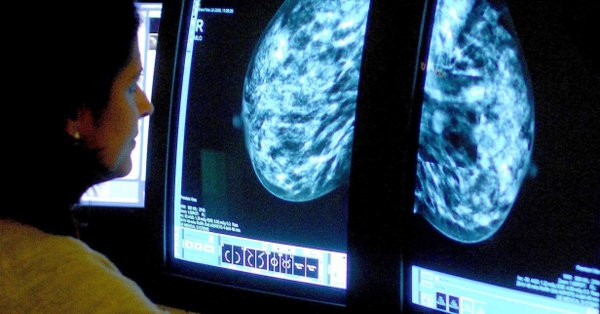

Google Health'de ve İngiltere'de Imperial College London üniversitesinde görevli bilim insanları, yaklaşık 29 bin kadının mamografi görüntülerini inceleyebilen yapay zeka geliştirdi.

Sonuçları Nature dergisinde yayımlanan çalışmada algoritmanın, mamogramları okurken, hastanın geçmişini bilmemesine rağmen iki doktorun birlikte teşhis koyması kadar doğru sonuçlar elde ettiği görüldü.

Yapay zekanın teşhislerinin tek bir doktorun koyduğu teşhisten daha doğru olduğu tespit edildi.

Tek bir radyolog ile kıyaslandığında yapay zekanın hatalı pozitif teşhis (mamogramın hatalı olarak anormal görülmesi) oranının yüzde 1.2, hatalı negatiflerinin de (kanserin gözden kaçırılması) yüzde 2.7 az olduğu belirtildi.